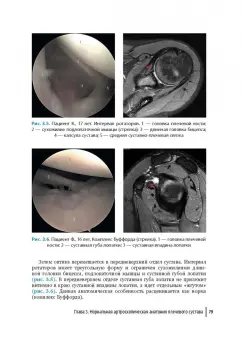

В атласе представлены наиболее частые патологические состояния коленного и плечевого суставов у детей, обусловленные в первую очередь травмами и их последствиями и вызванные процессами воспалительного и опухолевого генеза. Книга состоит из двух частей, каждая из которых содержит по две главы, посвященные нормальной и патологической анатомии. В начале глав приведена общая справочная информация в краткой форме. Артроскопические фотографии дополнены пояснениями. Для максимально эффективного восприятия информации специалистами и последующей самостоятельной практики материал представлен параллельно с данными лучевой диагностики (магнитно- резонансной и компьютерной томографии).